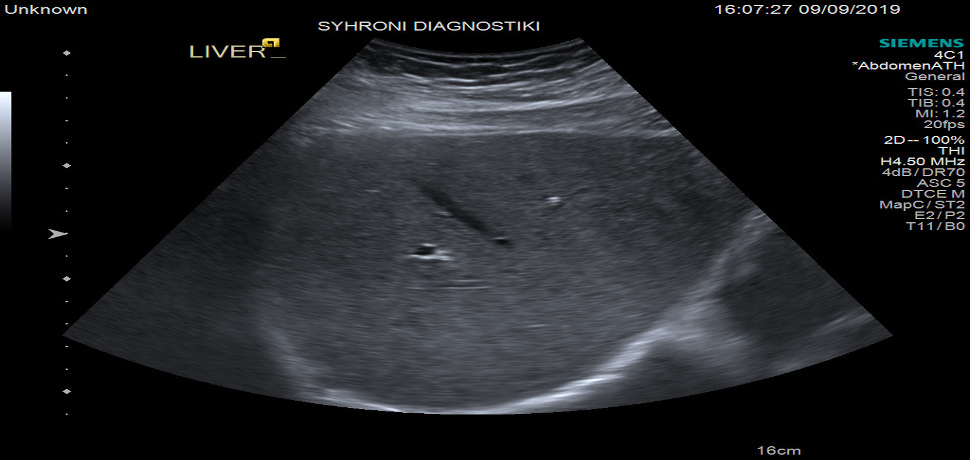

Χρησιμοποιείται σε περιπτώσεις διερεύνησης, όταν υπάρχει υποψία για κακοήθεια μιας βλάβης, με την καθοδήγηση ιατρού ακτινολόγου και των υπερήχων. Το δείγμα το οποίο λαμβάνεται στέλνεται για κυτταρολογική εξέταση.